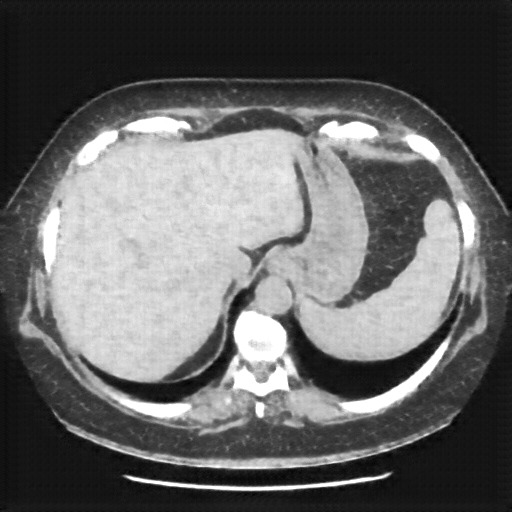

Reconstructed NATIVE CT scan (cycle consistency)

Full window (WL 1023.5, WW 4095 β†’ Low βˆ’1024, High +3071)

Actual HU range: [-1024.0, 544.7]